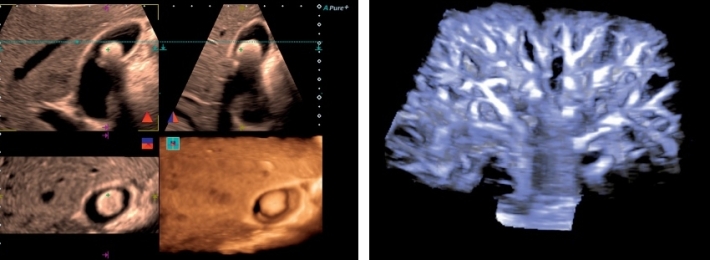

Изображения